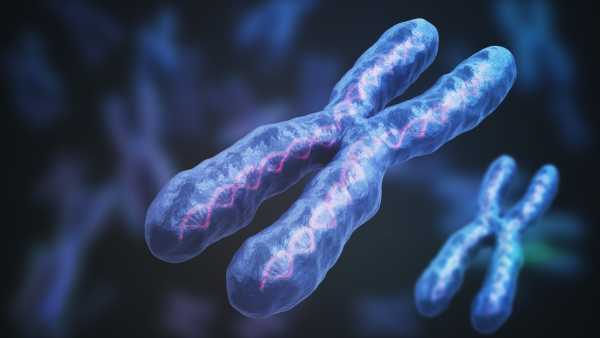

Жінки в 4 рази частіше хворіють на аутоімунні захворювання, ніж чоловіки. Можливо, причиною є Х-хромосома.